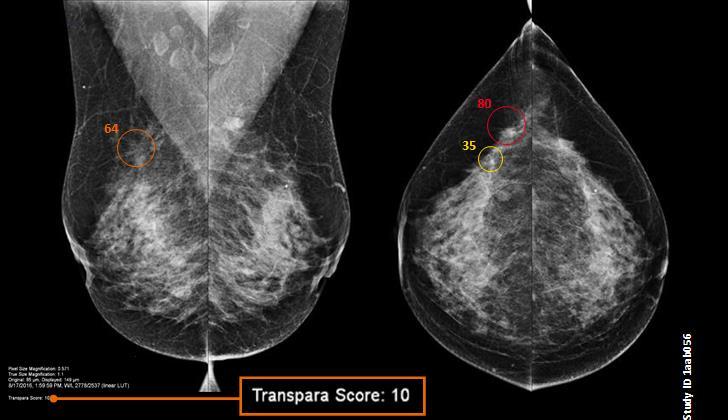

- Abnormality detection, acute infarction, acute hemorrhage, mass effect

Trained on 25,000 MRI studies

Oncology risk prediction Brain tumor and mets